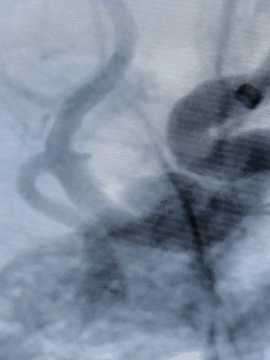

术后造影

术后正位即刻造影显示:Surpass Streamline血流导向密网支架整体贴壁良好,瘤腔内造影剂明显滞留。

术后Dyna CT重建: